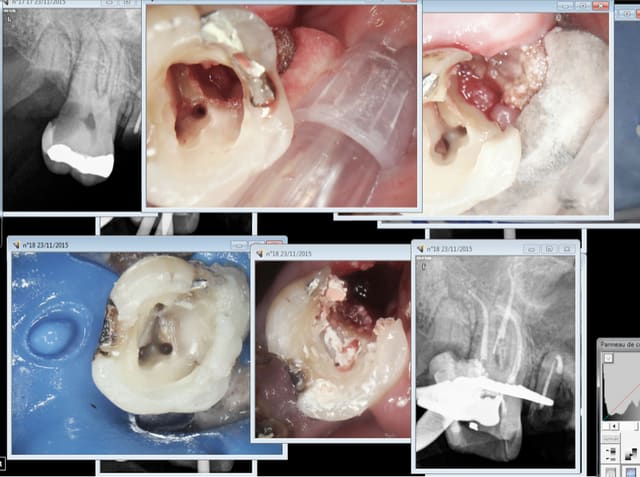

23/11/2015 à 14h15

Bon évidemment dans certains cas ca déborde un peu. -))))

Ca dégage meme lors de l'extraction de la dent distale. -)))))

Capture d e cran 2015 11 23 13.13 - Eugenol